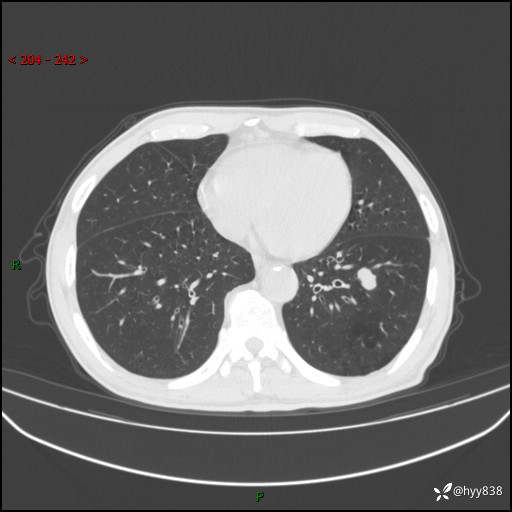

辅助检查:CT

胸部CT平扫